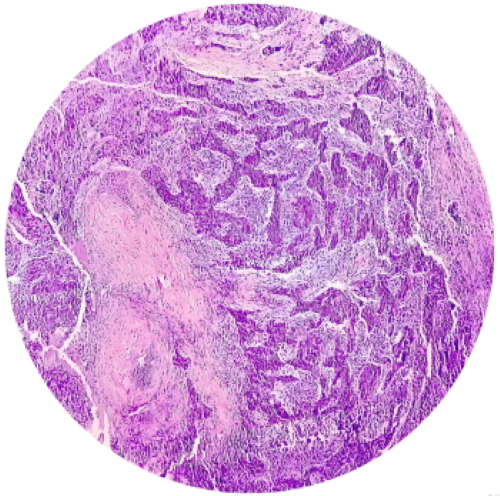

4. Fiberoptic Nasopharyngoscopy and Histological Biopsy: Fiberoptic nasopharyngoscopy allows for detailed, multi-angle observation of the nasopharyngeal mucosa. If a suspicious lesion is found, a small forceps can be inserted simultaneously to take a tissue biopsy from the site. Pathological examination of the biopsied tissue under a microscope provides a definitive diagnosis.